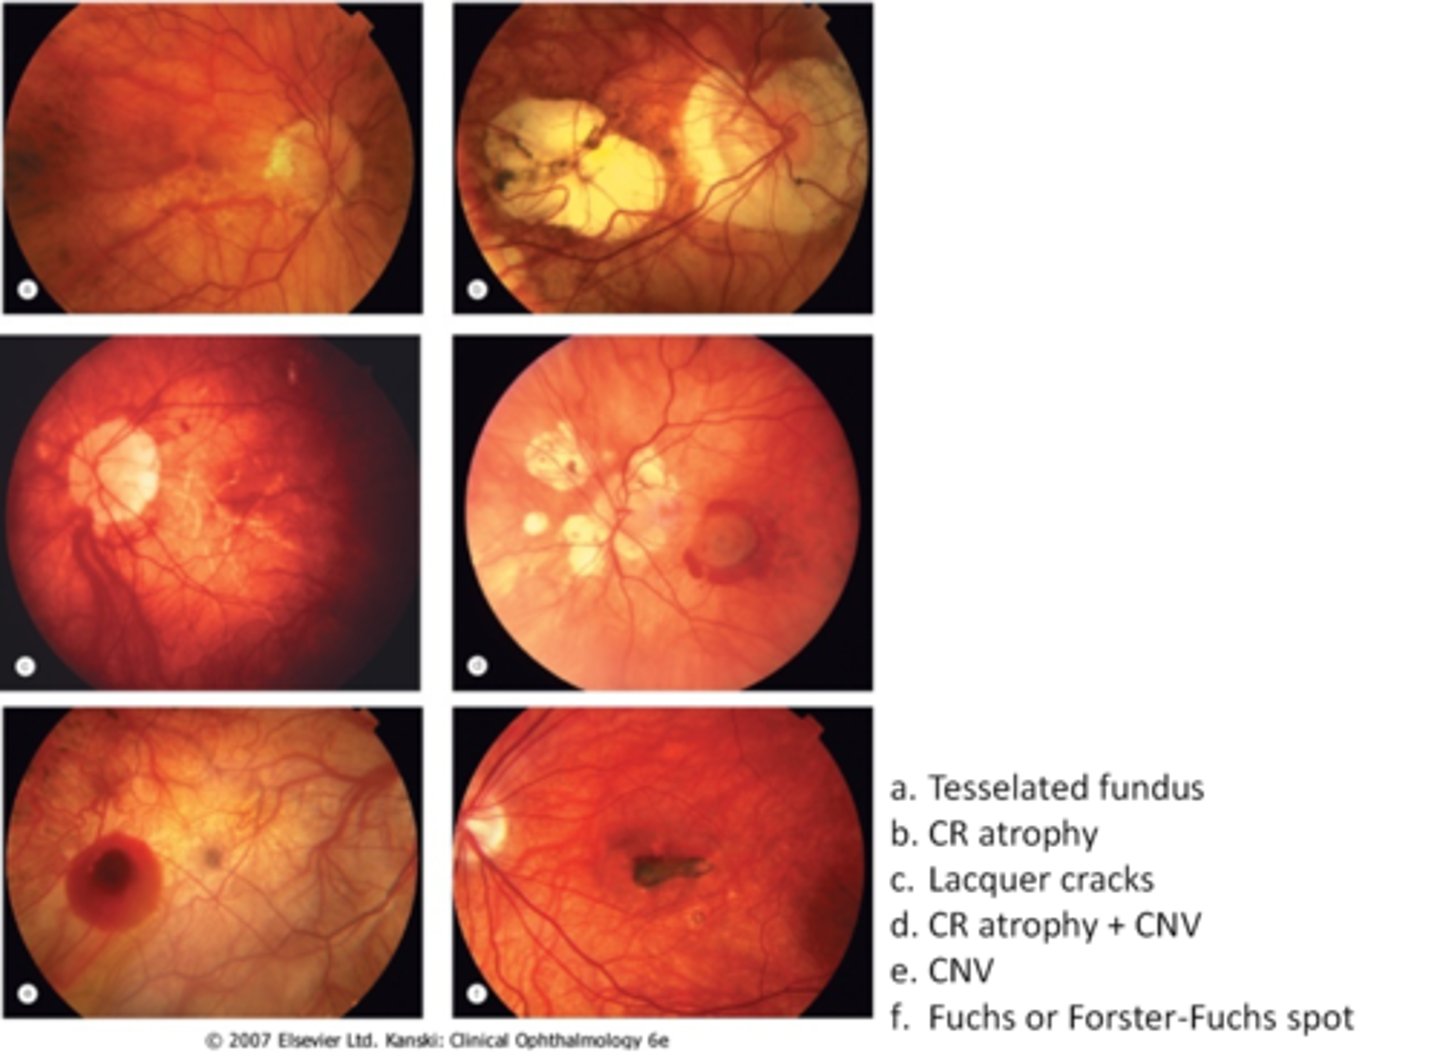

tesselated or tigroid fundus = visibility of choroidal vasculature (A)

What are some common findings in degenerative myopia?

lacquer cracks (C)

CNV (E)

chorioretinal atrophy (B)

What findings of degenerative myopia are seen here?

PPA

crescent

lacquer cracks

What are lacquer cracks and what causes them?

breaks in Bruch's membrane that can expand and contract, mostly seen in degenerative myopia

How do lacquer cracks appear on fundoscopy?

jagged, irregular yellow lines showing sclera in the posterior pole

What is the main complication of lacquer cracks?

CNV in 29% of pt's